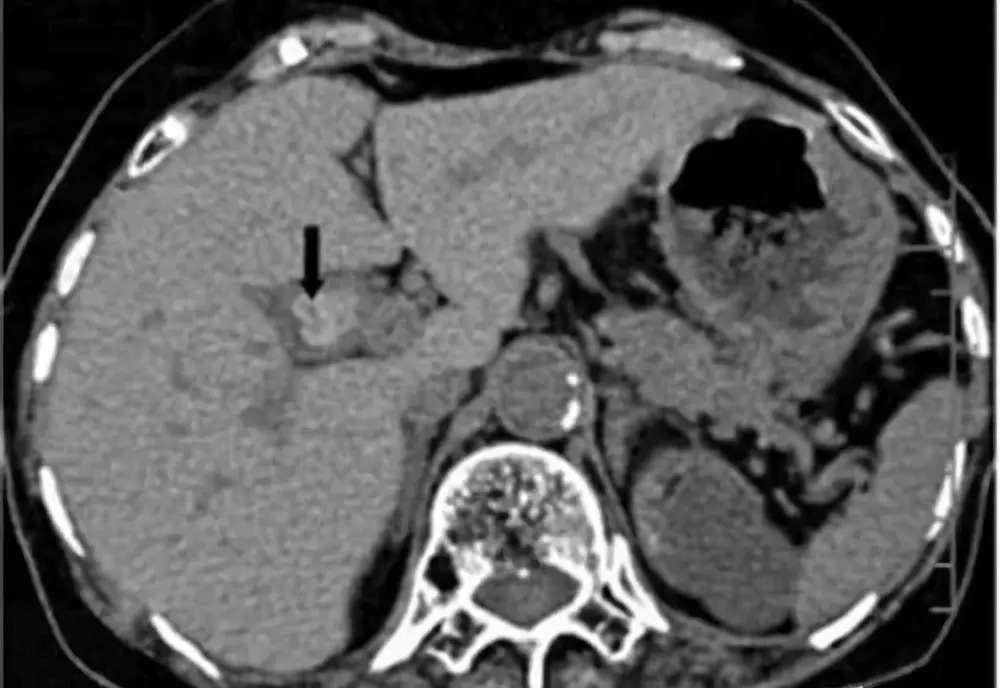

胆囊息肉

符合指征要手术

最近,陈女士在单位安排的每年一次体检时发现了胆囊里有一个0.4×0.6厘米大小的息肉,而且报告单上还显示:壁欠光滑。她听身边的人说胆囊息肉可能会癌变,一时慌了神,全家人也都非常担心她。

胆囊息肉是胆囊壁向腔内呈息肉样突起的一类病变的总称,包括肿瘤性息肉和非肿瘤性息肉,一般症状轻微,甚至无症状。目前胆囊息肉的病因尚不清楚,长期饮酒,高脂饮食,不吃早餐、压力大、熬夜及生活不规律者,容易得胆囊息肉。胆囊息肉以良性息肉更为多见,但也要预防癌变。

一旦发现就要定期复查,如果符合以下手术指征,建议尽早手术治疗。如胆囊单发息肉直径超过1厘米以上,蒂粗大者,尤其是基底宽,位于胆囊颈部,年龄超过50岁;胆囊多发息肉合并胆囊结石且有症状;胆囊息肉直径小于5毫米,无症状,要每3~6个月随访,迅速增大或症状明显等。